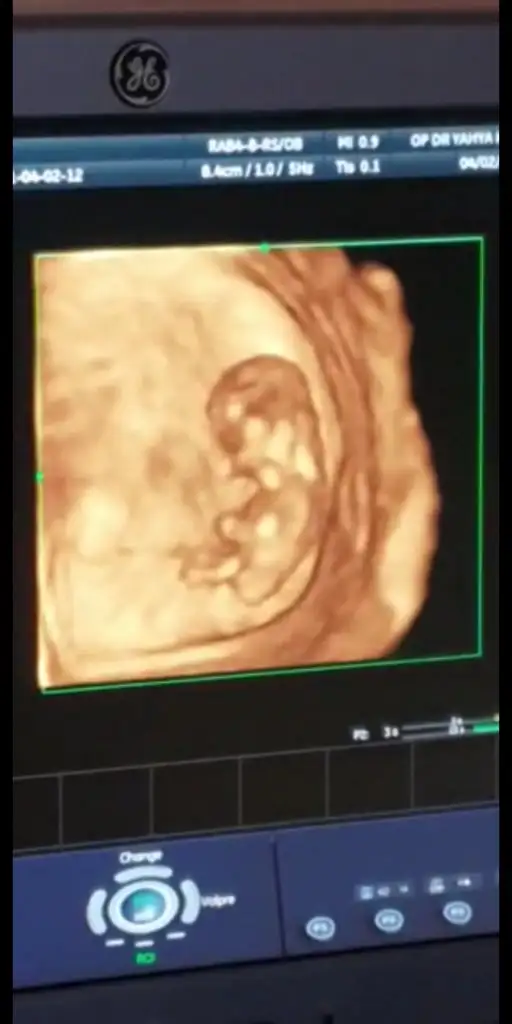

Bu da 3 boyutlu videodan kestiğim bir görüntü 2 hafta sonra tekrar paylaşırım ama hala kız gibi mi :)Sağlıkla gelsin minnos

Kız görünüyorBu da 3 boyutlu videodan kestiğim bir görüntü 2 hafta sonra tekrar paylaşırım ama hala kız gibi mi :) Eki Görüntüle 2816862